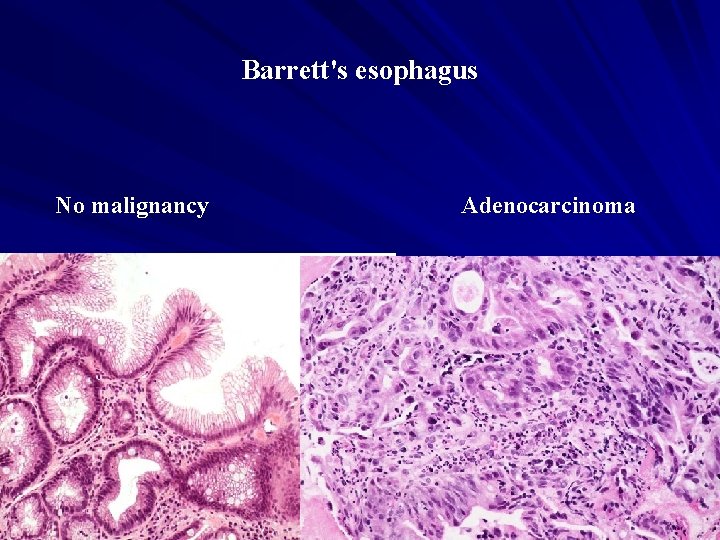

Barrett's esophagus No malignancy Adenocarcinoma

Barrett’s Esophagus A premalignant condition in which the normal stratified squamous epithelium of the esophagus is replaced by a metaplastic columnar epithelium as a complication of chronic gastroesophageal reflux disease (GERD). The metaplastic epithelium of Barrett's esophagus is variously called – – – Barrett's metaplasia, specialized columnar metaplasia intestinal metaplasia.

Red, velvety mucosa located between the smooth, pale pink esophageal squamous mucosa and the more lush, light brown gastric mucosa. Microscopically: – the esophageal squamous epithelium is replaced by metaplastic columnar epithelium. – dysplasia (the presumed precursor of malignancy)